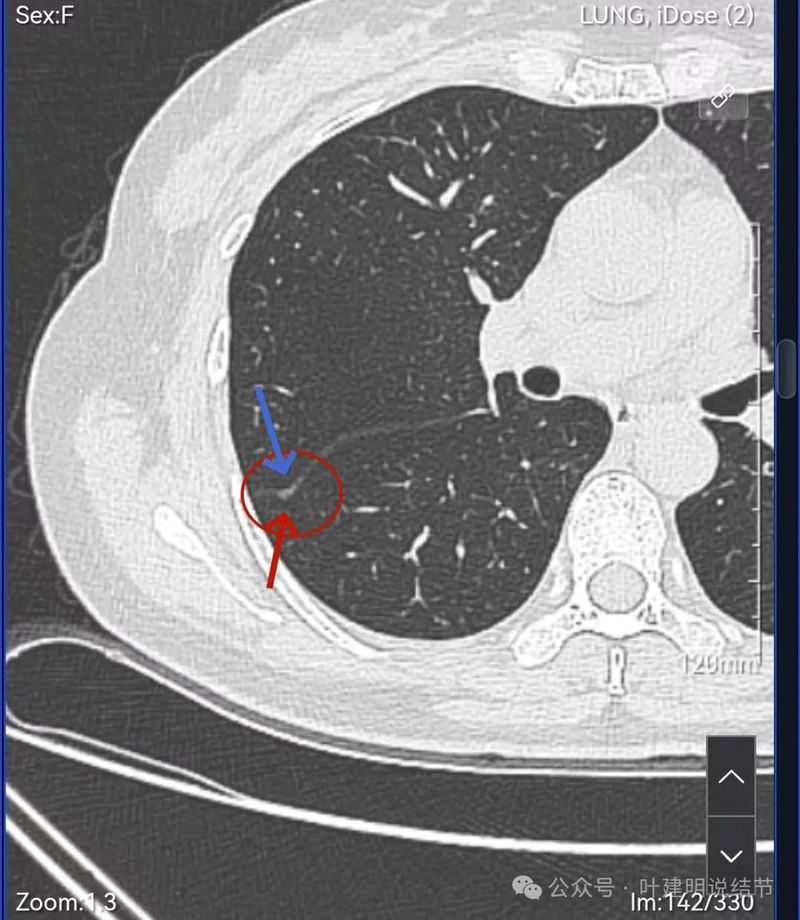

主病灶连续层面影像:

病灶出现,紧贴叶间裂。

轮廓清楚,叶间胸膜牵拉。